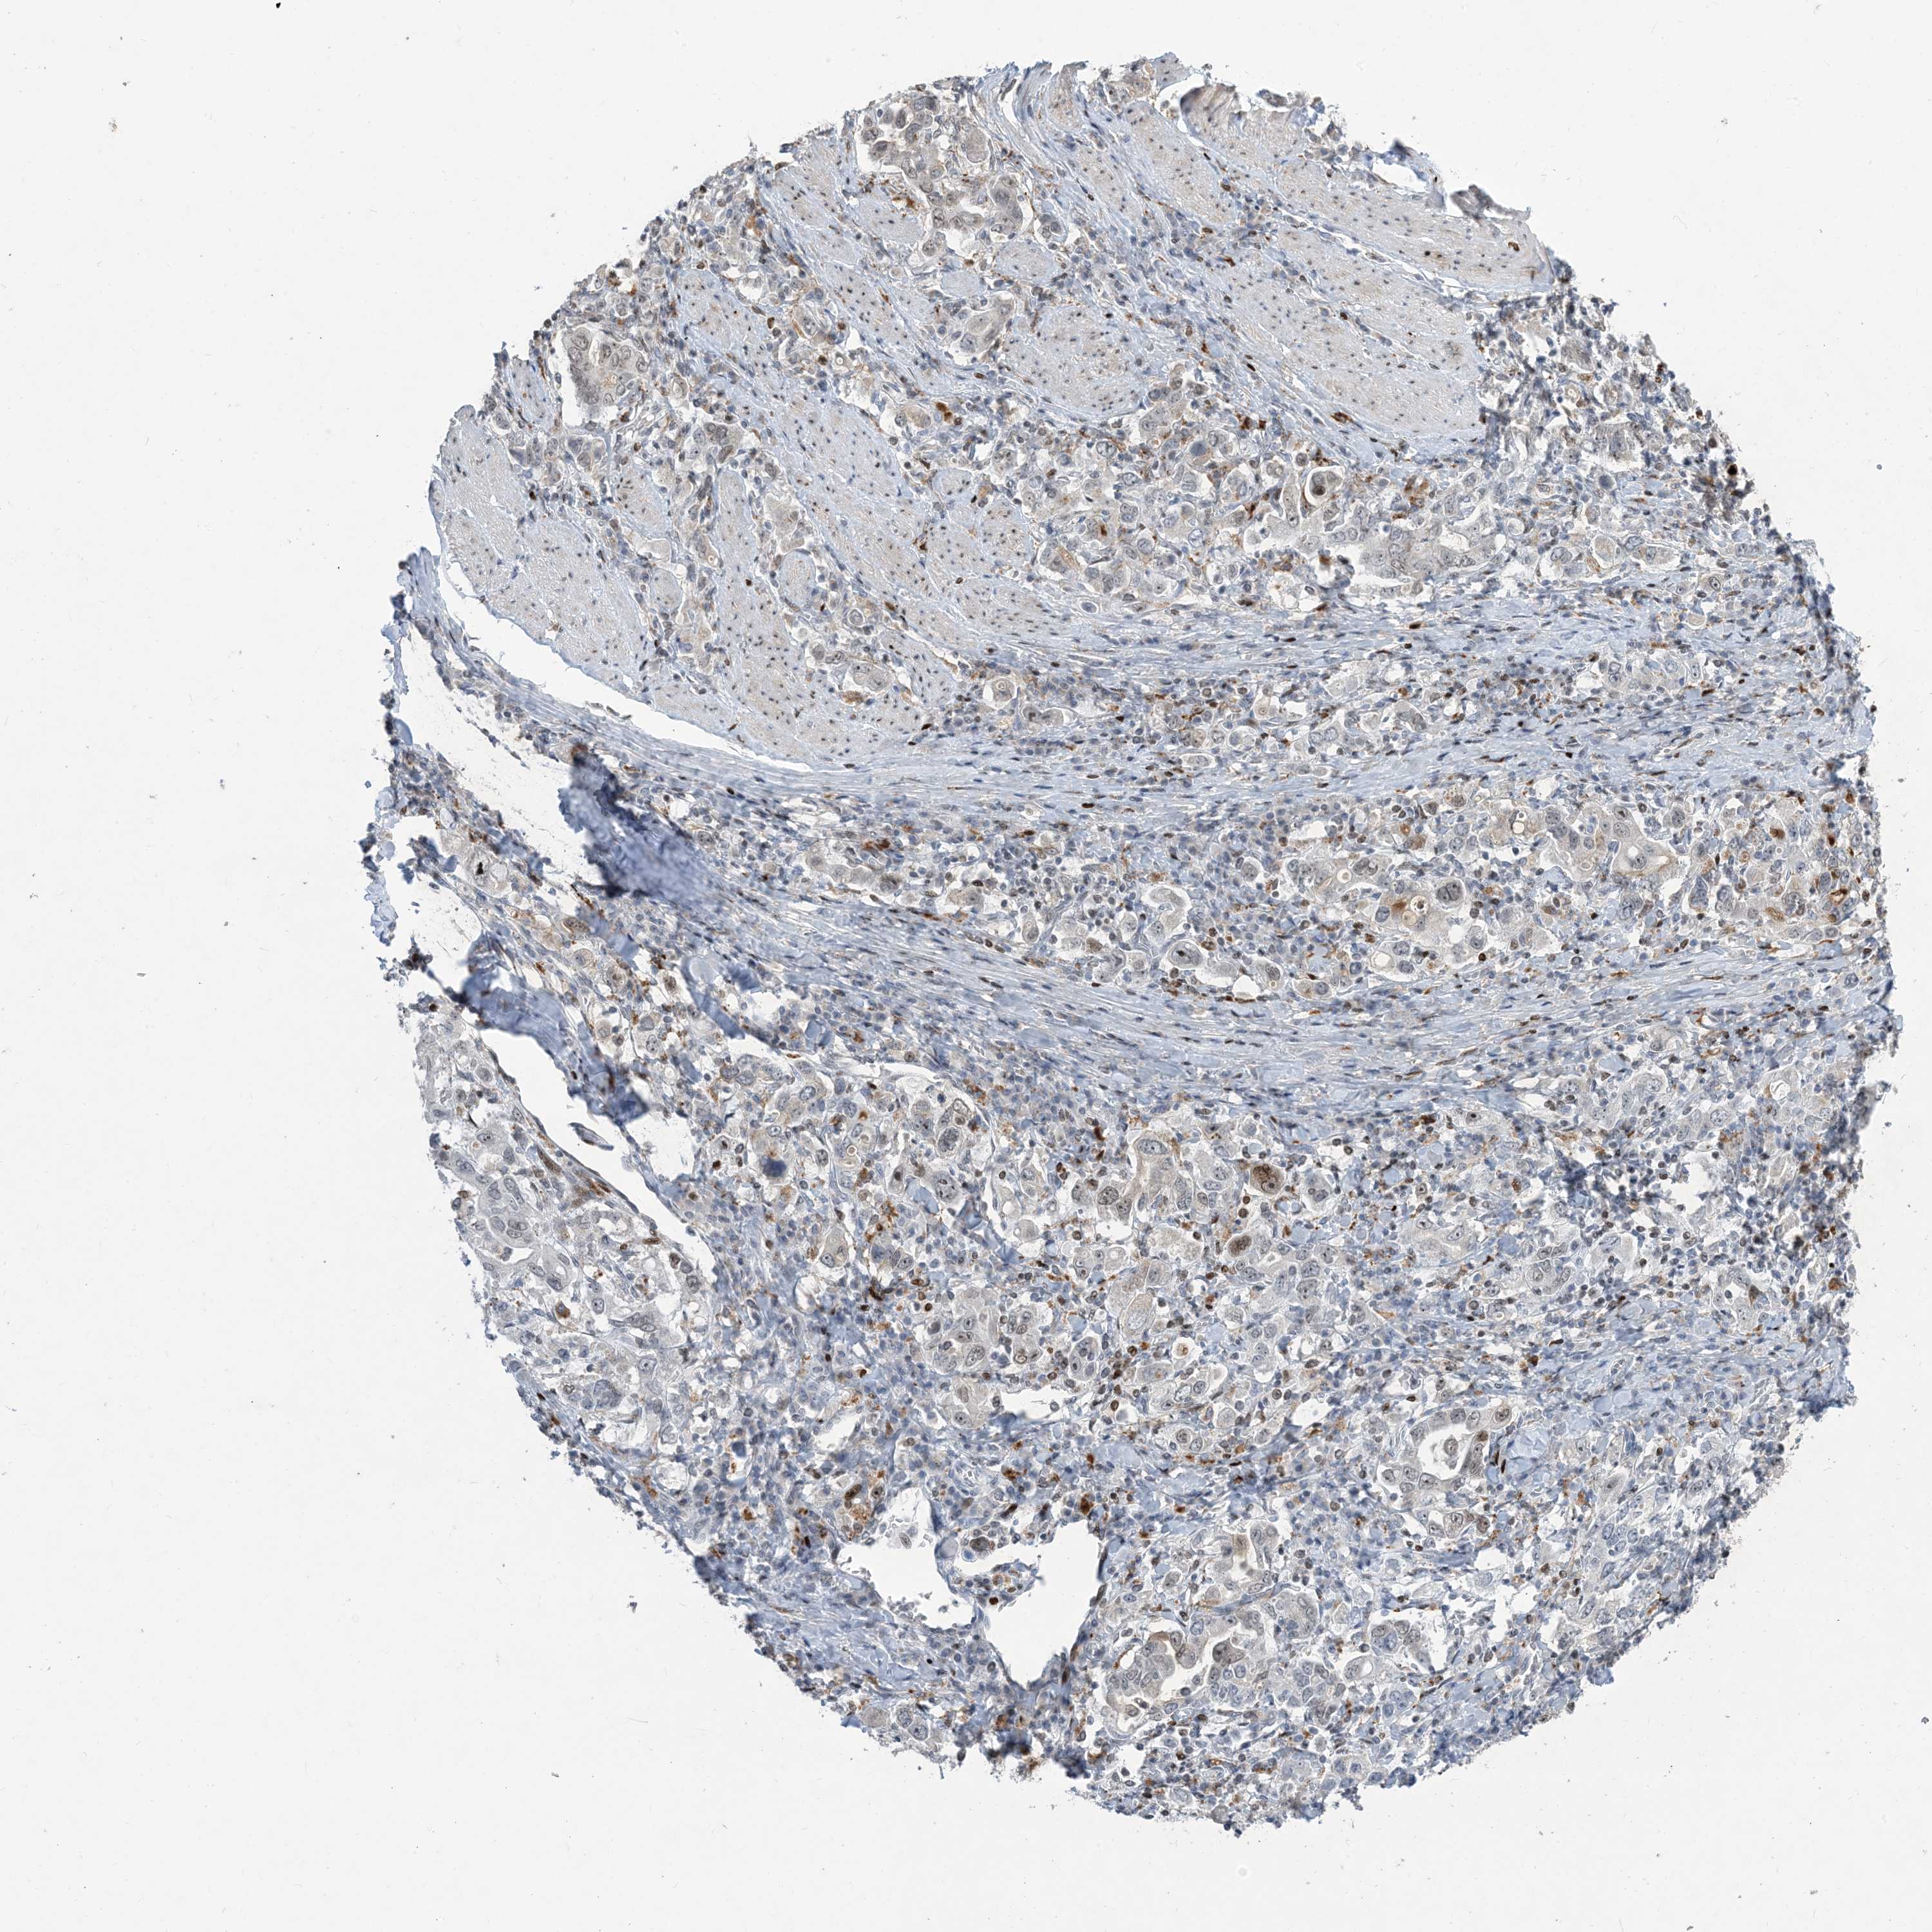

STOMACH CANCER - Protein expressioni

A mouse-over function shows sample information and annotation data. Click on an image to view it in a full screen mode. Samples can be filtered based on level of antibody staining by selecting one or several of the following categories: high, medium, low and not detected. The assay and annotation is described here.

Note that samples used for immunohistochemistry by the Human Protein Atlas do not correspond to samples in the TCGA dataset.

Antibody stainingi

Antibody staining in the annotated cell types in the current human tissue is reported as not detected, low, medium, or high, based on conventional immunohistochemistry profiling in selected tissues. This score is based on the combination of the staining intensity and fraction of stained cells.

Each image is clickable and will lead to virtual microscopy that enables deeper exploration of all samples and also displays staining intensity scores, fraction scores and subcellular localization as well as patient and tissue information for each sample.

Antibody HPA034959

Staining

High

Medium

Low

Not detected

Intensity

Strong

Moderate

Weak

Negative

Quantity

>75%

75%-25%

<25%

None

Location

Nuclear

Cytoplasmic/membranous

Cytoplasmic/membranous,nuclear

Adenocarcinoma, NOS